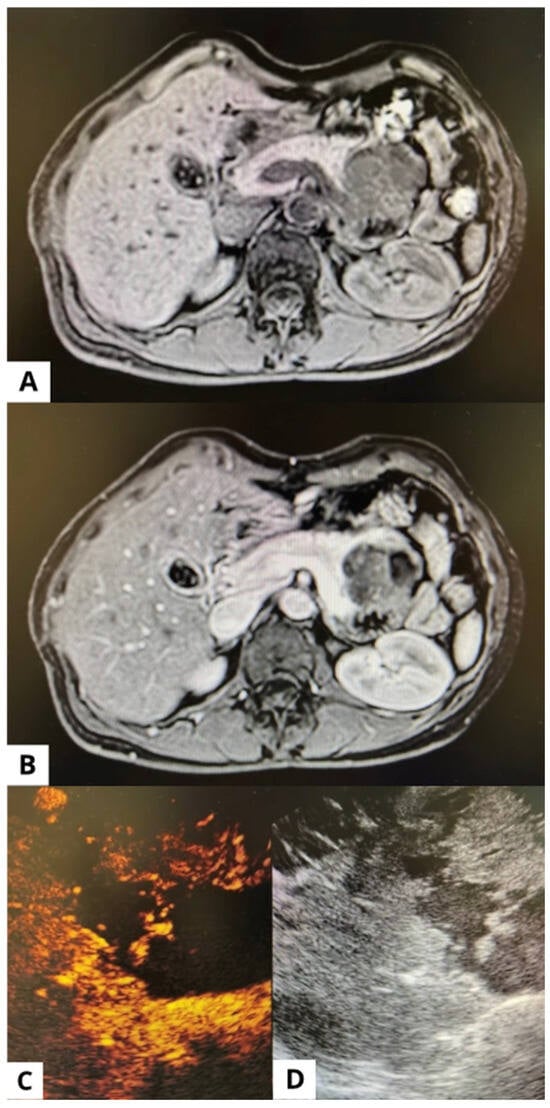

Comparison between imaging and EUS features is presented in Table 2. Figure 1 shows a case of SPN at MRI and EUS.

Figure 1. A case of solid pseudopapillary neoplasm. The same lesion shown in (A) MRI without contrast, (B) MRI with contrast, (C) EUS post contrast medium, and (D) EUS before contrast medium.